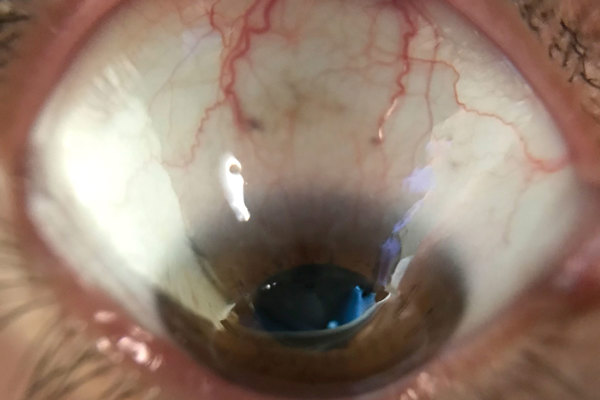

Crystalline keratopathy in monoclonal gammopathy of undetermined significance